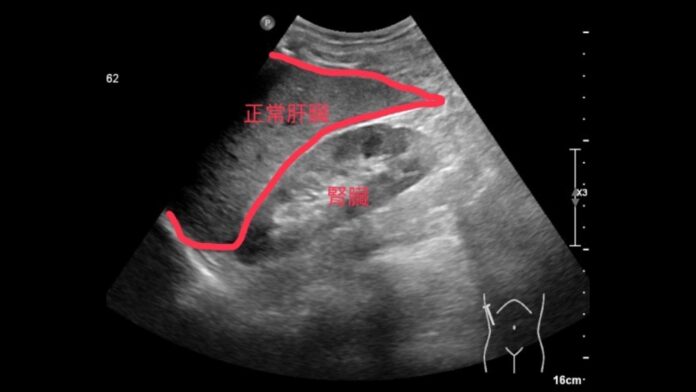

(觀傳媒彰化新聞)【記者陳雅芳/彰化報導】我看起來不胖,為什麼會得脂肪肝?一名45歲的男性業務主管,外型勻稱、體重正常,平時也不暴飲暴食,日前因公司健檢發現肝功能指數偏高,前往彰化秀傳紀念醫院進一步檢查。經腹部超音波檢查,發現有輕度脂肪肝,後續抽血追蹤顯示三酸甘油酯指數也明顯偏高。

「內臟脂肪才是關鍵。」謝偉耀解釋,即使外表體型正常,但若內臟脂肪過高,仍可能導致脂肪堆積於肝細胞中,進而引發脂肪肝。這類族群常見於代謝異常者,尤其是三酸甘油酯代謝能力較差者,更容易出現肝臟脂肪過多的情況。